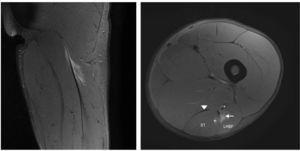

Un jugador de fútbol profesional de dieciocho años sufrió el mismo tipo de dolor en las mismas circunstancias. Los signos clínicos eran exactamente similares a los del caso de los isquiotibiales agudos descrito, pero la prueba de RM mostró imágenes diferentes (figs. 3 y 4) porque la lesión estaba localizada en el tendón libre del bíceps femoral. La longitud del tendón libre fue 8,5 cm y la lesión fue localizada a 6,5 cm de la tuberosidad isquiática. Debido al largo período de recuperación y a un alto índice de relesión, debía considerarse el tratamiento quirúrgico. Por tanto, se realizó la escisión del tejido cicatricial, incluyendo la parte rasgada del tendón y la sutura sin tensión del remanente del vientre del bíceps femoral al semitendinoso adyacente, con el fin de proporcionar tensión al tendón y refuerzo con anclaje en la tuberosidad isquiática (figs. 3 y 4).

Figura 3 Vista intraoperatoria. Tendón libre (FT), nervio ciático (SN), semitendinoso (ST) y porción larga del bíceps femoral (LHBF).